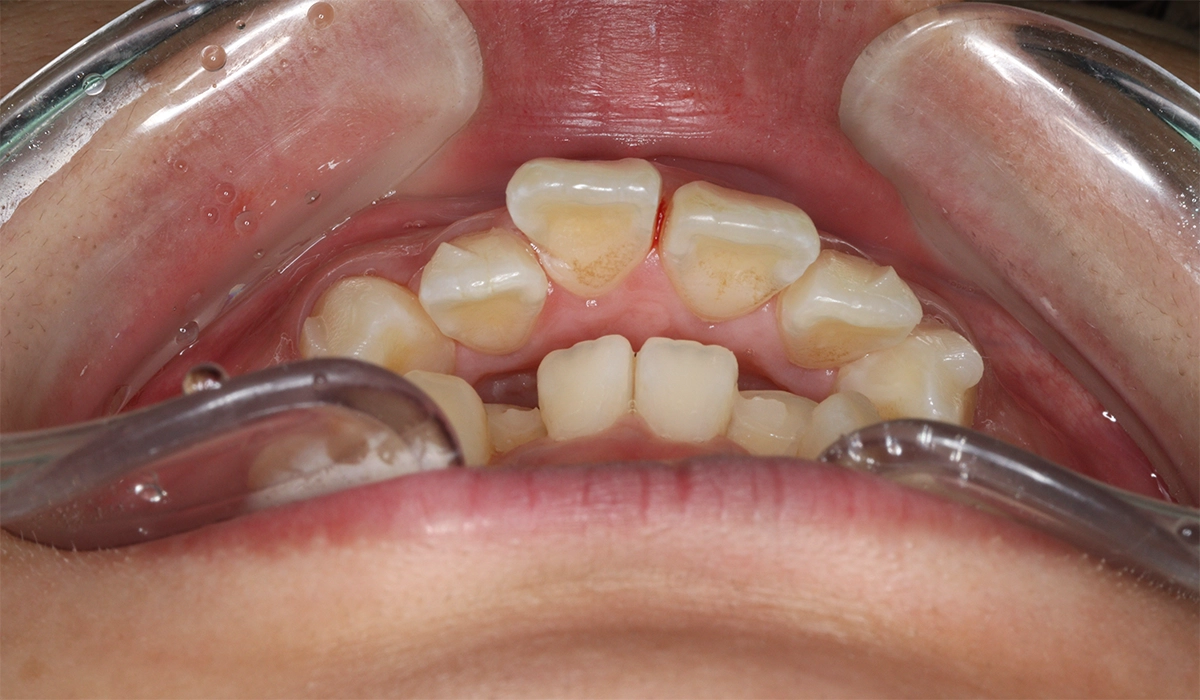

術前:上顎

術前:下顎